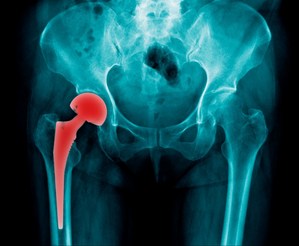

What is a Hip Injury?Our hips are located on either side of our pelvis. A joint is formed where the tops of the thigh bones meet the pelvis. This fit, referred to as a ball-and-socket joint, allows for movement and rotation in the legs and pelvis. The hips bear much of our body weight and are constantly used as we walk, run, and exercise. The hips are subject to considerable wear and tear over the course of a lifetime and, as a result, become weaker with age. Some common injuries to the hip can include the following:

- Dislocation: This occurs when the bones shift out of position. For example, when a sudden fall jolts the thigh bone out of the hip socket. A dislocation can be either partial or full, and in some instances, surgery may be required to reset the joint.

- Fracture: A broken bone or fracture is a common side effect of a fall, although sometimes they result from overuse. A broken bone is usually accompanied by pain, swelling, bruising, and limited mobility.